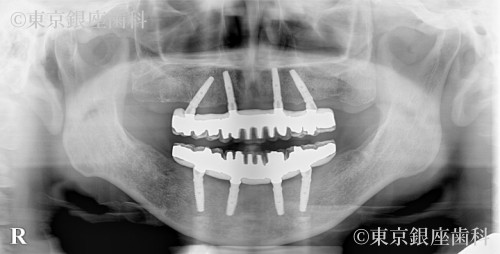

After

幼少期からの歯科恐怖症で長期間治療を避けてきたが、家族の結婚式のため治療を決断。丁寧な説明で不安を軽減し、ワンデイインプラントで当日に仮歯を装着したことで自然な見た目で式に参加できた。

ワンデイインプラント(上下)